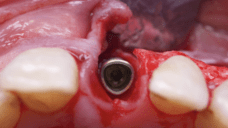

The surgical protocol began with the atraumatic extraction of tooth 1.1 to preserve as much of the alveolar socket as possible. Immediately following extraction, an N1 implant was placed into the socket using a guided surgical approach to ensure ideal three-dimensional positioning. The “one abutment one time” technique was applied to minimize soft tissue manipulation during the healing phase, which is particularly important in esthetic areas.

Given the significant buccal defect, guided bone regeneration (GBR) was performed simultaneously. A mixture of autologous bone and creos™ xenogain™ was applied to the defect and covered with a resorbable creos™ membrane to restore ridge width and support the buccal contour. In addition, a connective tissue graft was harvested and placed in the vestibular region to increase the thickness of keratinized mucosa. This combined approach addressed both hard and soft tissue deficiencies, providing the biological foundation for a stable and esthetic outcome.